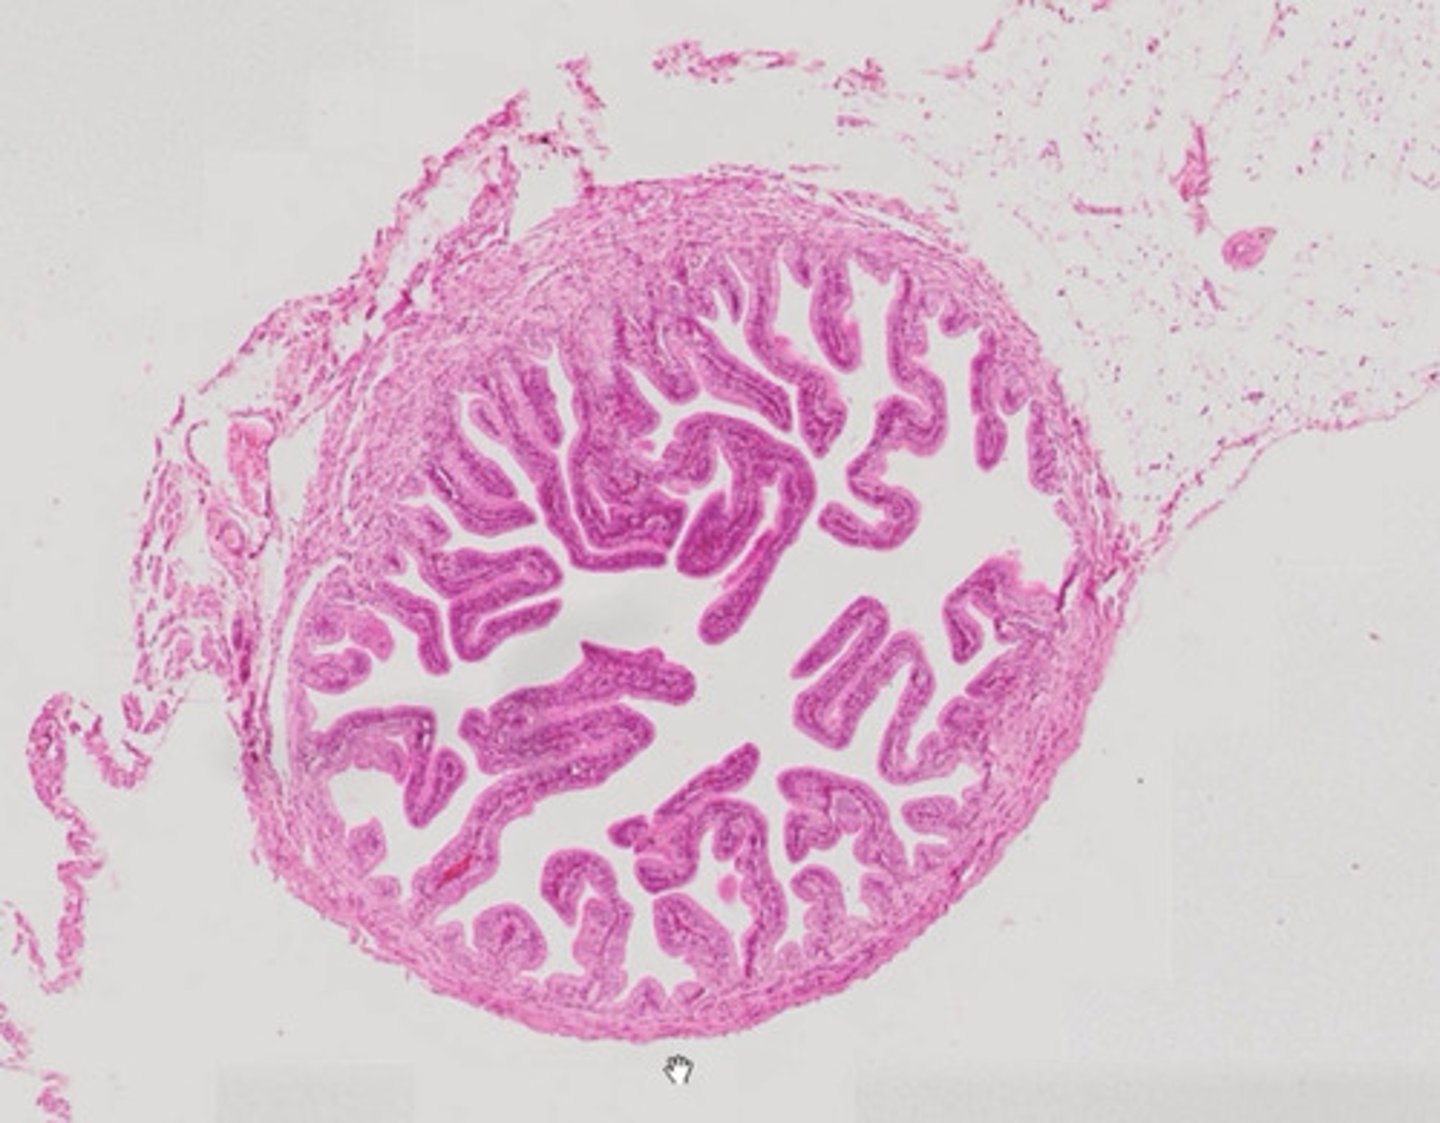

Jajowód (H+E)